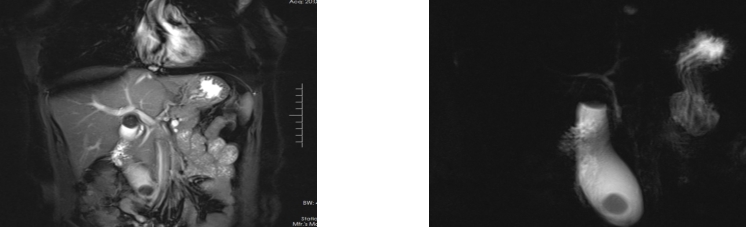

图1 MRI+MRCP诊断为I型MS患者影像学资料Fig.1 Imaging data of patients diagnosed with type I MS by MRI+MRCP